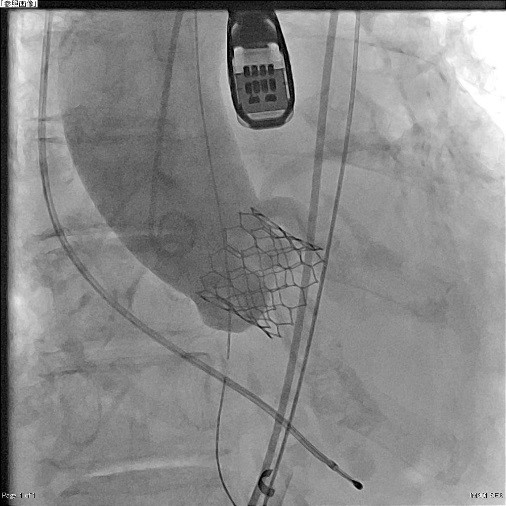

両心室ペーシング機能付き植込型除細動器移植術

両心室ペーシング機能付き植込型除細動器移植術

(X線撮影)

治療では、狭窄した冠動脈を風船で広げ、ステントと呼ばれる金属でできた網目状のデバイスを留置する冠動脈拡張術(PCI)や、不整脈の原因となる電気回路の遮断のために心筋を高周波電流で焼却するアブレーション治療、ペースメーカーや植込み型除細動器などのデバイス埋め込み術などがあります。

治療では、狭窄した冠動脈を風船で広げ、ステントと呼ばれる金属でできた網目状のデバイスを留置する冠動脈拡張術(PCI)や、不整脈の原因となる電気回路の遮断のために心筋を高周波電流で焼却するアブレーション治療、ペースメーカーや植込み型除細動器などのデバイス埋め込み術などがあります。